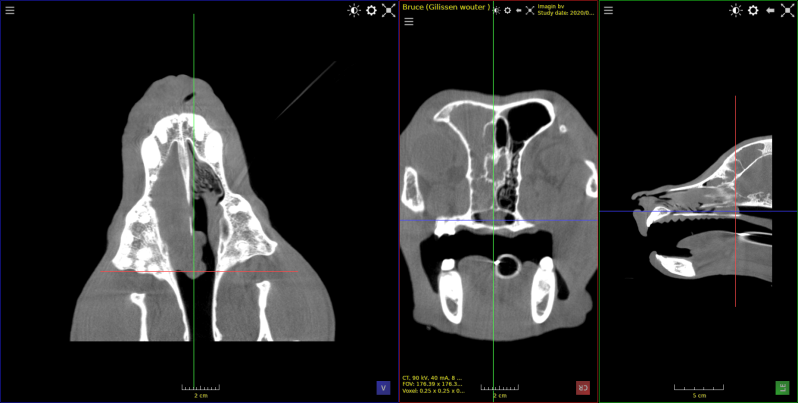

Hond Fila braziliero , van 7 maanden met tandwortel abces .

Gedeelte van het bot rond de tandwortel was aangetast .